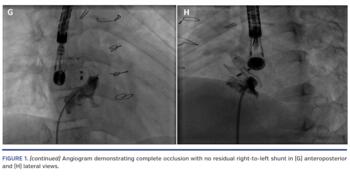

Cardiac catheterization was performed via femoral approach and revealed a right atrial pressure of 10 mm Hg with a pulmonary to systemic blood flow ratio of 0.9. Multiple attempts were made to advance wires into the left atrium along the ASDO without success. However, each wire passed around the waist of the ASDO in a circular fashion (Figures 1B and 1C; Video 1). After advancing the wedge catheter along the wire, angiography revealed a “doughnut-shaped” leak in a 360° loop along the waist of the ASDO connecting the right and left atrium (Figures 1D and 1E; Video 2). We elected to close this channel using a 6 x 6 mm Amplatzer Duct Occluder II (ADO2). A Glidewire (Terumo Medical) was advanced along the waist into the left atrium and the Glide catheter (Terumo Medical) was advanced into the left atrium. Several wires were used to secure the position; however, we could not advance the 5 Fr Flexor delivery sheath (Cook Medical) across the full loop due to high tortuosity within the ASDO. Therefore we advanced the ADO2 180° around the loop and deployed the device (Figure 1F; Video 2). Repeat angiogram showed complete occlusion with no right-to-left shunt (Figures 1G and 1H; Video 2). The device was released and repeat EAS confirmed no residual shunt. The patient subsequently had near complete resolution of her migraines.